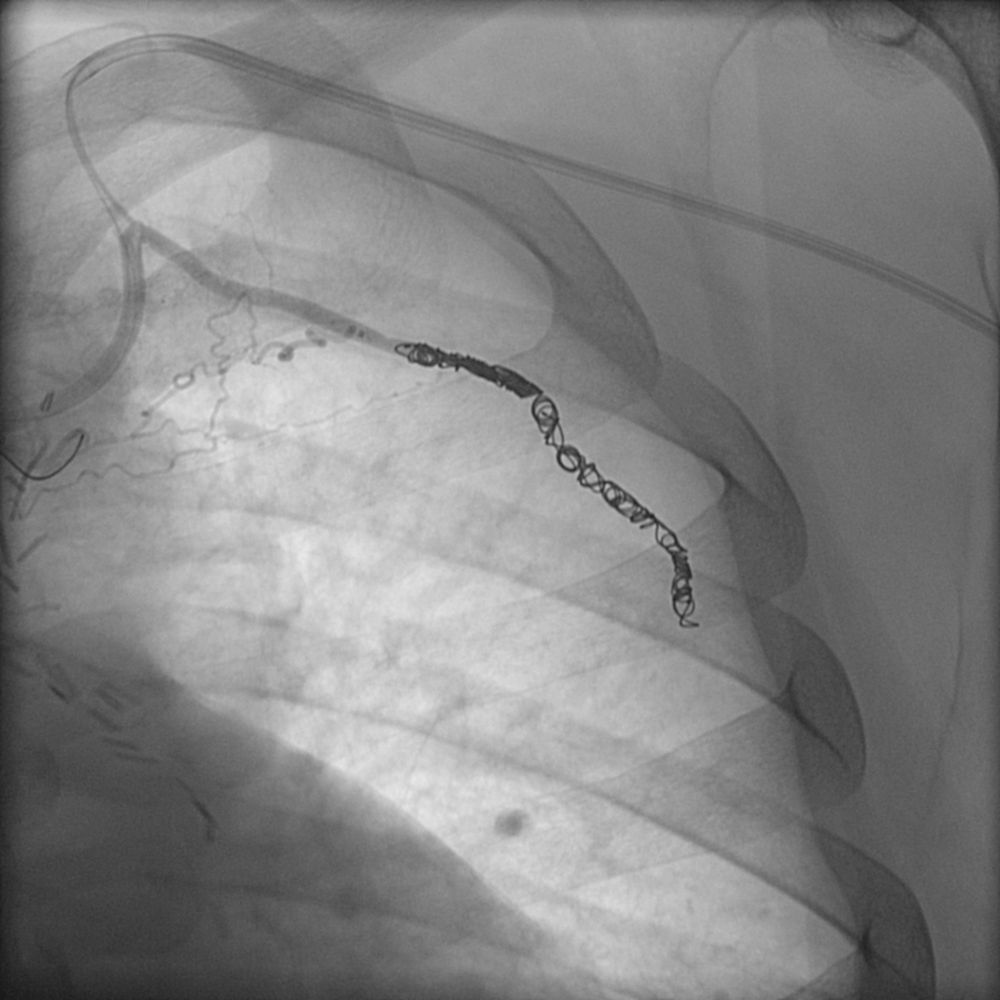

Συνοπτικά υπό την καθοδήγηση του αγγειογράφου, αναγνωρίζεταιτο παθολογικό αγγείο-αγγεία και με ειδικούς καθετήρες και μικροκαθετήρες, διοχετεύονται εμβολικά υλικάόπως μικροσφαιρίδια ή coils, ώστε να αποφραχθεί ή να μειωθεί η παθολογική αγγείωση.